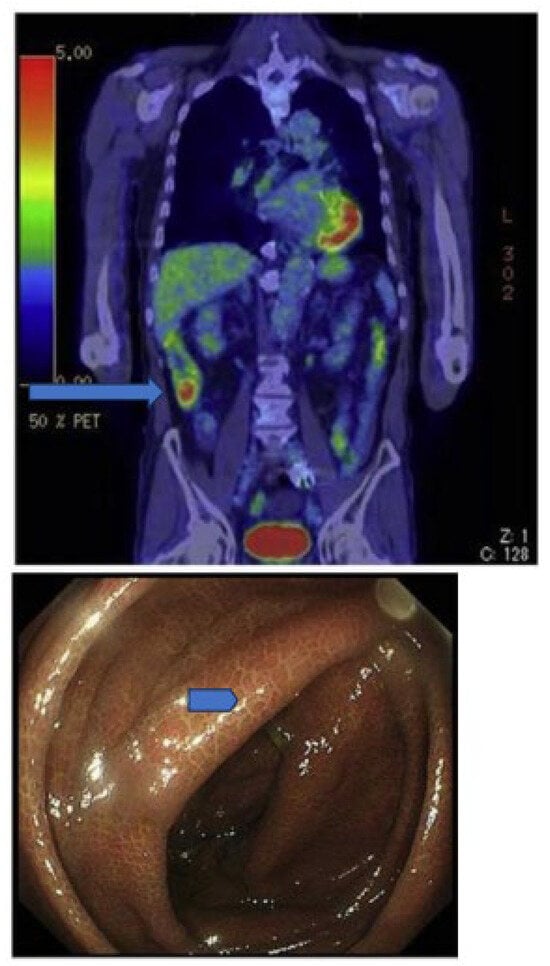

Morita and coworkers [171], by using positron emission tomography (PET)-MRI, recently found that the maximum standardized uptake value (SUVmax) of F18-FDG in the intestine (jejunum, ileum, and right or left hemicolon) of metformin-treated diabetics was higher than that of the control group. More importantly, the study permitted to differentiate the SUVmax of the intestinal wall from that of the intestinal lumen. The SUVmax of the intraluminal space in metformin-treated diabetics was greater than that of the controls (Figure 2). On the contrary, the SUVmax of the intestinal wall was similar in both groups [171]. A temporarily increased accumulation of the injected tracer seems to be observed (Figure 3) also in the liver of metformin-treated diabetics up to 48 h after interruption of the oral uptake of the drug [171,172,173], suggesting a persisting uptake of the radioactive glucose mediated by circulating insulin as consequence of the “metabolic starvation”(?) induced by the biguanide.

Figure 2.

PET-images taken 60 min after intravenous administration of F18-FDG in a diabetic patient treated with metformin (A) and in a control patient (B). In (A), radioactivity has accumulated in the last portion of the ileum and in the colon (right hemicolon, stronger than left hemicolon). The indication for the study was that gall bladder cancer was confirmed by the accumulation of the tracer in the gallbladder (arrow). From Morita Y et al. [171].

Figure 3.

PET scan was performed in diabetics at different times after interruption of metformin therapy. In patient 4, interruption time was shorter than 48 h and showed strong accumulation of the tracer in the colon. From Schreuder N et al. [173].

Accumulation of F18-FDG in the large intestine (Figure 4) has been found also in persons who regularly use laxatives [175,176]. SUVmax can even reach levels that simulate those of colorectal neoplasms (Figure 5) in patients with chronic constipation [177].

Figure 4.

PET pictures of early scans (upper row) and of late FDG scans (lower row) after oral administration of laxatives. The arrows in the upper row of PET scans show the different patterns of accumulation of the tracers in the large intestine. From Chen Y-K et al. ([176], with permission).

Figure 5.

Accumulation of radioactivity after intravenous administration in the coecum and ascending colon (upper panel, long arrow) of a patient using anthraquinone laxatives, as demonstrated by the presence of melanosis coli at colonoscopy performed to exclude colon cancer (lower panel, short arrow). From Katsumata R [177].